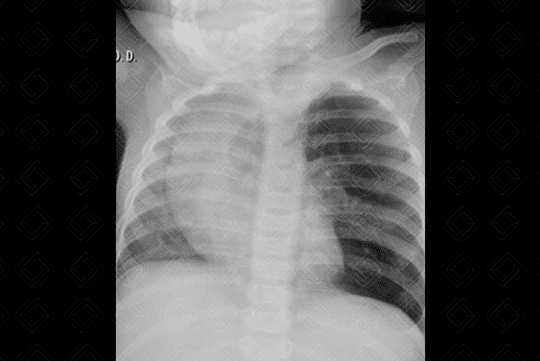

Texto alternativo para a imagem Créditos: Dra. Elazir Mota - Rio de Janeiro/RJ

Descrição da imagem: Radiografia de tórax AP. Hipertransparência no lobo superior do pulmão esquerdo, com desvio do mediastino contralateralmente. Silhueta cardiotímica com dimensões normais.

A hiperinsuflação lobar congênita , c onhecida também por enfisema lobar congênito (nomenclatura antiga), ocorre por uma anomalia na cartilagem brônquica, levando à progressiva hiperinsuflação do segmento ou lobo pulmonar acometido. A localização mais comum é o lobo superior esquerdo.

• Radiografia do tórax: Inicialmente (principalmente no primeiro e segundo dias de vida), a radiografia de tórax pode estar com uma hipotransparência difusa, por acúmulo do líquido que ainda não foi totalmente absorvido. Para melhor avaliação desta malformação, o exame deve ser feito após as primeiras 48 horas quando observa-se uma hipertransparência, com principal local de acometimento no lobo superior esquerdo (seguido em frequência pelos lobo médio e superior direito);